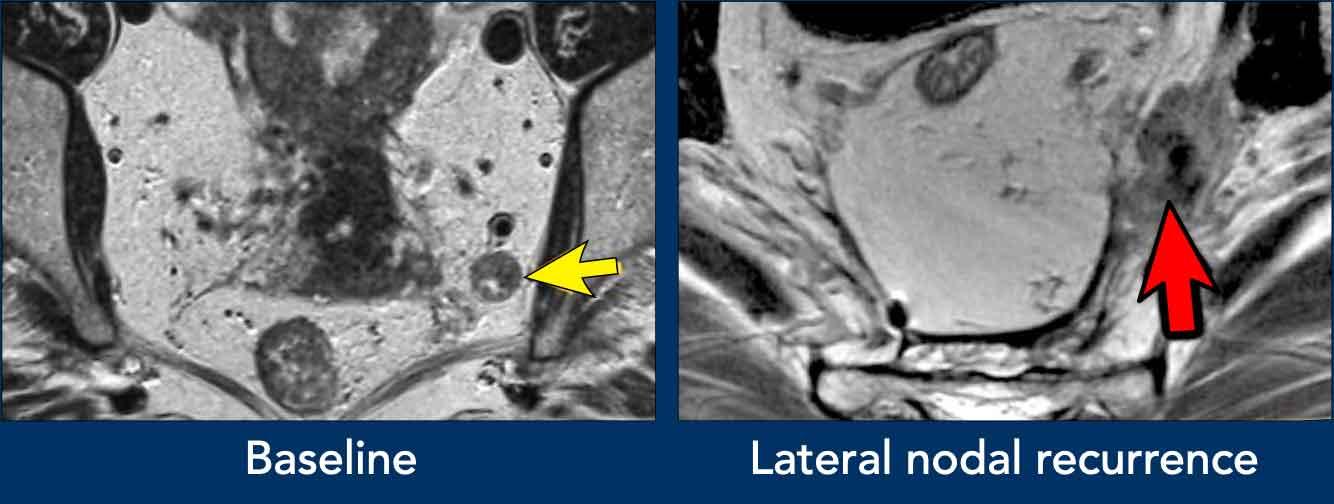

Hình ảnh

- Hình ảnh bên trái: Hạch bạch huyết bệnh lý 9 mm ở khoang bịt bên trái (mũi tên), được xác định tại thời điểm phân loại giai đoạn ban đầu. Cần xạ trị và/hoặc cắt bỏ riêng biệt để tránh tái phát bên ngoài.

- Hình ảnh bên phải: Bệnh nhân được điều trị bằng phương pháp TME tiêu chuẩn (không cắt hạch bên) đã xuất hiện khối u không đều ở khoang bịt trái, phù hợp với tái phát hạch bên.